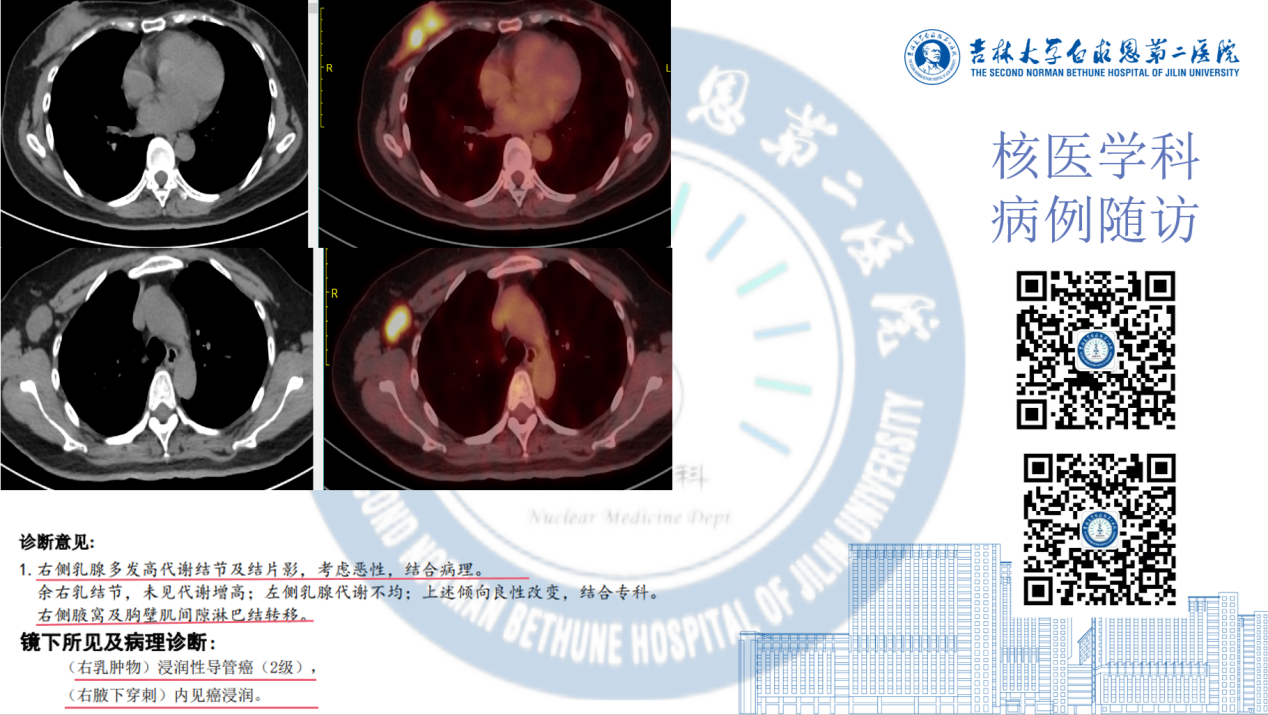

PET/CT精准定性乳腺病变性质并评估淋巴结转移情况。